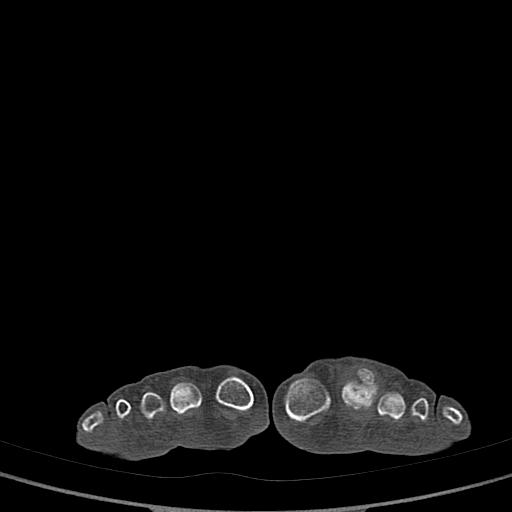

标题: CT13415:M72Y,跖趾关节病变,请会诊 [打印本页]

标题: CT13415:M72Y,跖趾关节病变,请会诊

男72岁左侧跖趾关节肿痛15年,查压痛。